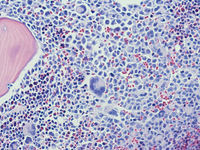

Mast cell Leukemia aspirate smears

Bone marrow aspirate shows diffuse infiltration of mast cells in various stages of maturation. Large atypical multinucleated forms can be seen at higher magnification